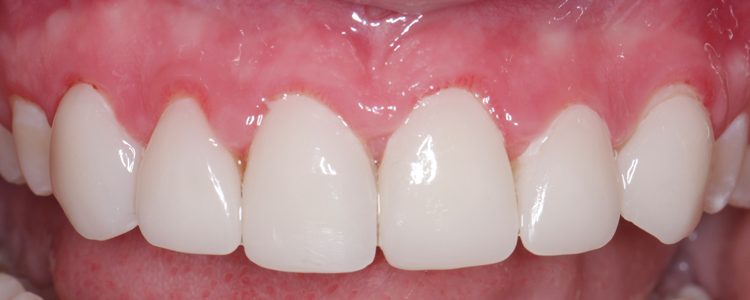

(10.) Retracted posttreatment view of the crowns after they were stained and glazed and placed with resin cement.

Figure 10